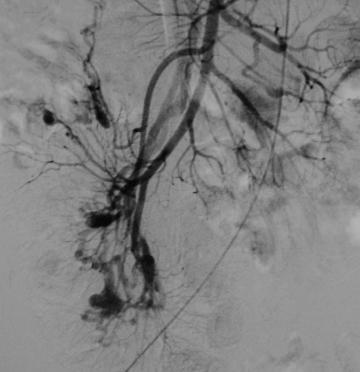

Histológicamente, se parece a la telangiectasia y el desarrollo está relacionado con la edad y la tensión en la pared intestinal.[5] Es una lesión degenerativa, adquirida, probablemente como resultado de una contracción crónica e intermitente del colon que obstruye el drenaje venoso de la mucosa. A medida que pasa el tiempo, las venas se vuelven cada vez más tortuosas, mientras que los capilares de la mucosa se dilatan gradualmente y el esfínter precapilar se vuelve incompetente. Así se forma una malformación arteriovenosa caracterizada por un pequeño penacho de vasos dilatados.[6]